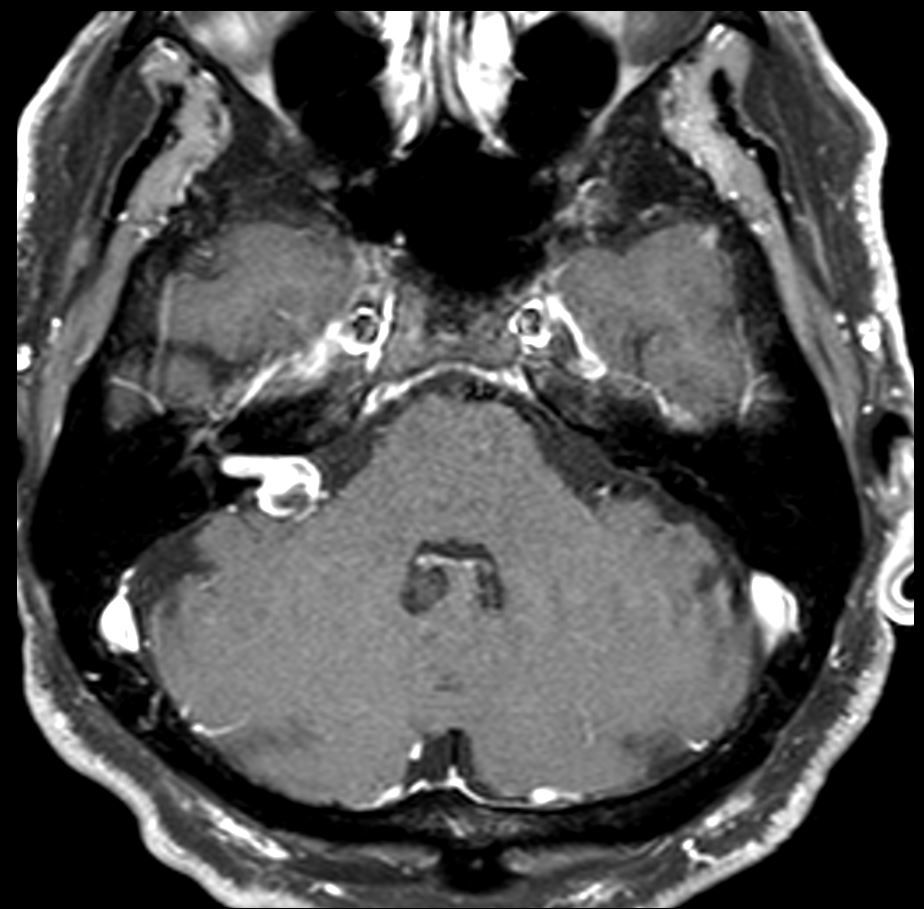

An elderly male presented with symptoms of vertigo. What is the most likely imaging finding?